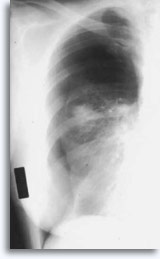

Fluoroscopie is de minst vaak gebruikte modaliteit voor longlaesies, omdat de vooruitgang in CT-beelden en de snelheid van beeldgeneratie de doeltreffendheid van aspiratie bevorderd hebben. Een conventionele door fluoroscopie gestuurde FNAB met naald in doelgebied wordt hieronder weergegeven.

|

Nadat de basislijnbeelden voltooid zijn, wordt de patiënt schoongemaakt met een antisepticum en onder een laken gelegd om een steriel gebied te creëren. Er wordt lokale anesthesie gegeven en daarna wordt de flexibele 22 gauge spinale naald met de stilet op zijn plaats via de huid naar de vooraf geplande diepte ingebracht in de laesie [thoracale en abdominale laesies]. In andere gevallen wordt 22 gauge naald, bevestigd aan een 20 cc injectiespuit, in het doelgebied gebracht onder ultrasonografische besturing. De punt van de naald wordt geverifieerd. Als er gebruik wordt gemaakt van een stilet, wordt deze verwijderd. De injectiespuit wordt aan de naald bevestigd en de zuiger wordt vacuüm gezogen, terwijl de naald meerdere malen wordt geoscilleerd in verschillende vlakken. Terwijl de drukbalans gevolgd wordt, wordt de naald uit de patiënt verwijderd. Deze wordt vervolgens van de injectiespuit losgemaakt, lucht wordt aan de injectiespuit toegevoegd en deze wordt dan weer terug bevestigd aan de naald. Het materiaal wordt uit de naald op objectglaasjes gedrukt, en dan direct ondergedompeld in 95% ethanol. De naald wordt dan afgespoeld met een zoutoplossing, de ThinPrep® flacon, of in RPMI. Voor thoracale-abdominale laesies en lymfknopen blijft de patient meestal op lokatie, terwijl de objectglaasjes snel worden gekleurd en beoordeeld op geschiktheid, triage en diagnose. Schildklieren worden normaliter onderworpen aan 3 uitstrijken per doelgebied met het materiaal gekleurd en beoordeeld na voltooiing van de ultrasoundprocedure.